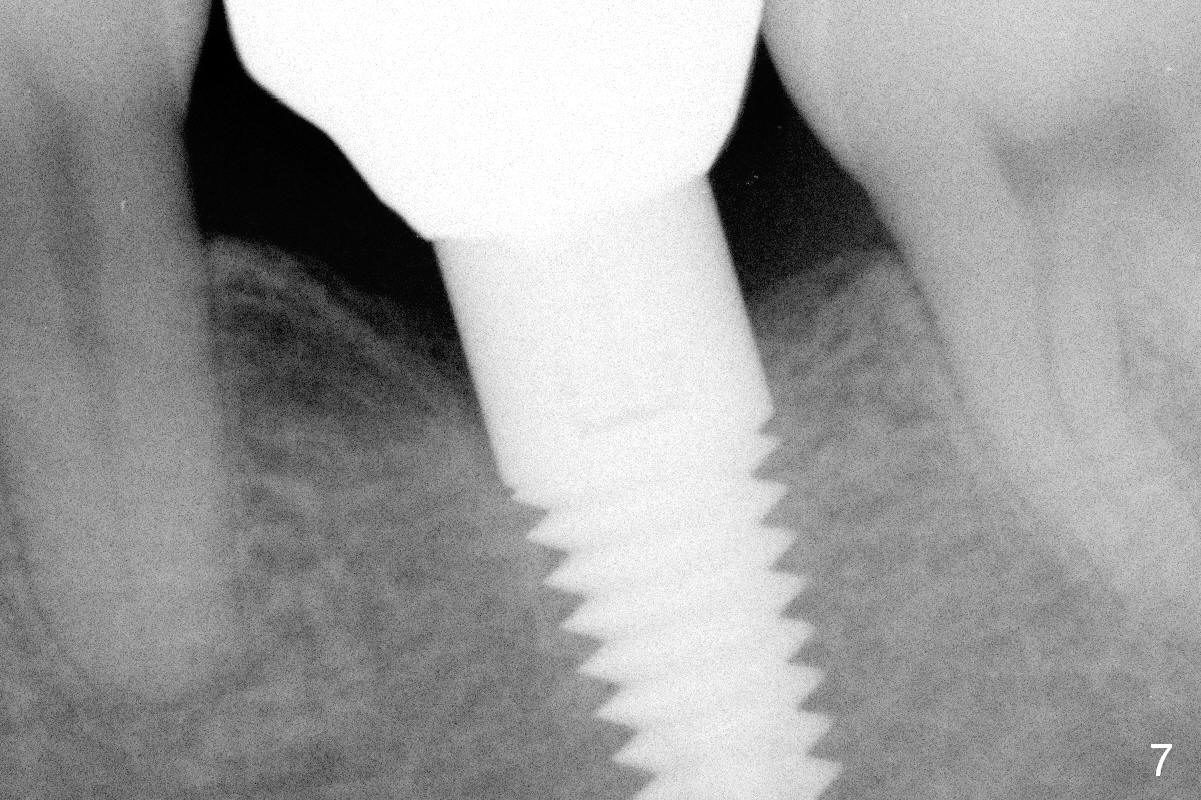

The mesial and distal crests of the tooth #19 were even for a 50-year-old man 7 years ago. Three years later, swelling developed around the distal root with bone loss (Fig.2 *). Three months later, localized swelling occurred (Fig.3 *) with oozing. The patient had thrombopenia (platelet 40 K). The tooth was extracted with suture. There is distolingual root tip resorption. Two months and a half later (Fig.4), a 6x17 mm implant was placed (Fig.5). The implant osteointegrated 5 months postop (Fig.6). The distal crest re-appears 5 months (Fig.7), 2 years (Fig.8) and 2 years 8 months (Fig.10) post cementation. At the last appointment, the patient complained of pain and swelling at #30 with mesial bone loss (Fig.10 *), as compared to Fig.9 taken 9 years ago. The mesiolingual pocket is deep. After scaling and Chlorhexidine irrigation, Arestin is locally administered.